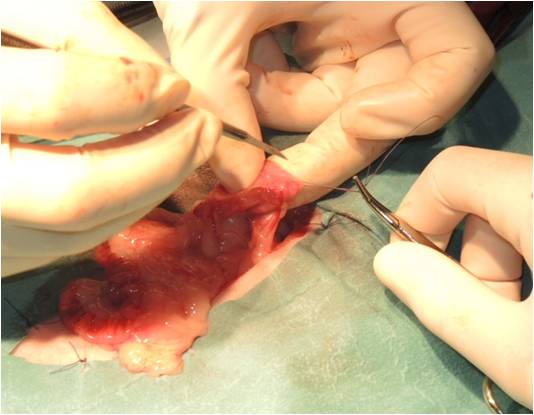

Lorsque les glandes surrénales sont fortement stimulées, elles deviennent progressivement hyperplasiques puis tumorales (tumeur bénigne puis maligne). Le diagnostic peut être établi par échographie, réalisée par un vétérinaire expérimenté avec les furets, et par une prise de sang (dosage des hormones en question). Suivant l'extension et la présence ou non d'embole vasculaire, il est recommandé de poser un implant hormonal ou de réaliser une surrénalectomie. Cette chirurgie est particulièrement risquée à cause de la proximité des glandes surrénales avec l'aorte, un vaisseau sanguin vital pour l'organisme. Il peut être utile d'utiliser des outils de microchirurgie ainsi que du matériel de pointe tel qu'une caméra endoscopique per-opératoire Vitum pour maximiser la réussite de la chirurgie.

Le diagnostic se fait par prise de sang et par échographie, réalisée par un vétérinaire expérimenté. Parfois, un traitement doit être administré en urgence, car les crises d'hypoglycémie peuvent être mortelles. Une hospitalisation est nécessaire en cas de crises convulsives. Les premières phases du traitement sont médicales mais une chirurgie (pancréatectomie) peut être recommandée dans certaines formes d'insulinome. Nous utilisons pour ce faire la technologie Ligasure pour minimiser le temps opératoire et les risques associés à l'opération.